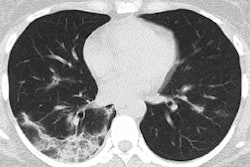

CT image of a 58-year-old woman with adenovirus infection showing ill-defined patchy ground-glass opacities and segmental and subpleural consolidations in both lungs, with most lesions along bronchovascular bundles. Image courtesy of the AJR."It is valuable for radiologists to recognize that the CT findings of COVID-19 overlap with the CT findings of diseases caused by viruses from a different family, such as adenovirus, and have differences as well as similarities with viruses within the same family," Li and Xia wrote.

Among the patient cohort, the most common CT findings were ground-glass opacities and consolidation with or without vascular enlargement (96.1% of patients), followed by interlobular septal thickening (70.6%), air bronchogram sign (68.6%), and air trapping (11.8%). Most of these findings were similar to CT features previously reported in patients with severe acute respiratory syndrome (SARS) and Middle East respiratory syndrome (MERS).

The researchers did identify CT findings that distinguished COVID-19 from SARS and MERS in several cases: the presence of a reversed halo sign in 3.9% of patients and pulmonary nodules with a halo sign in 17.6%. In addition, COVID-19 patients more frequently had multifocal involvement on CT, compared with unifocal involvement for SARS and MERS.